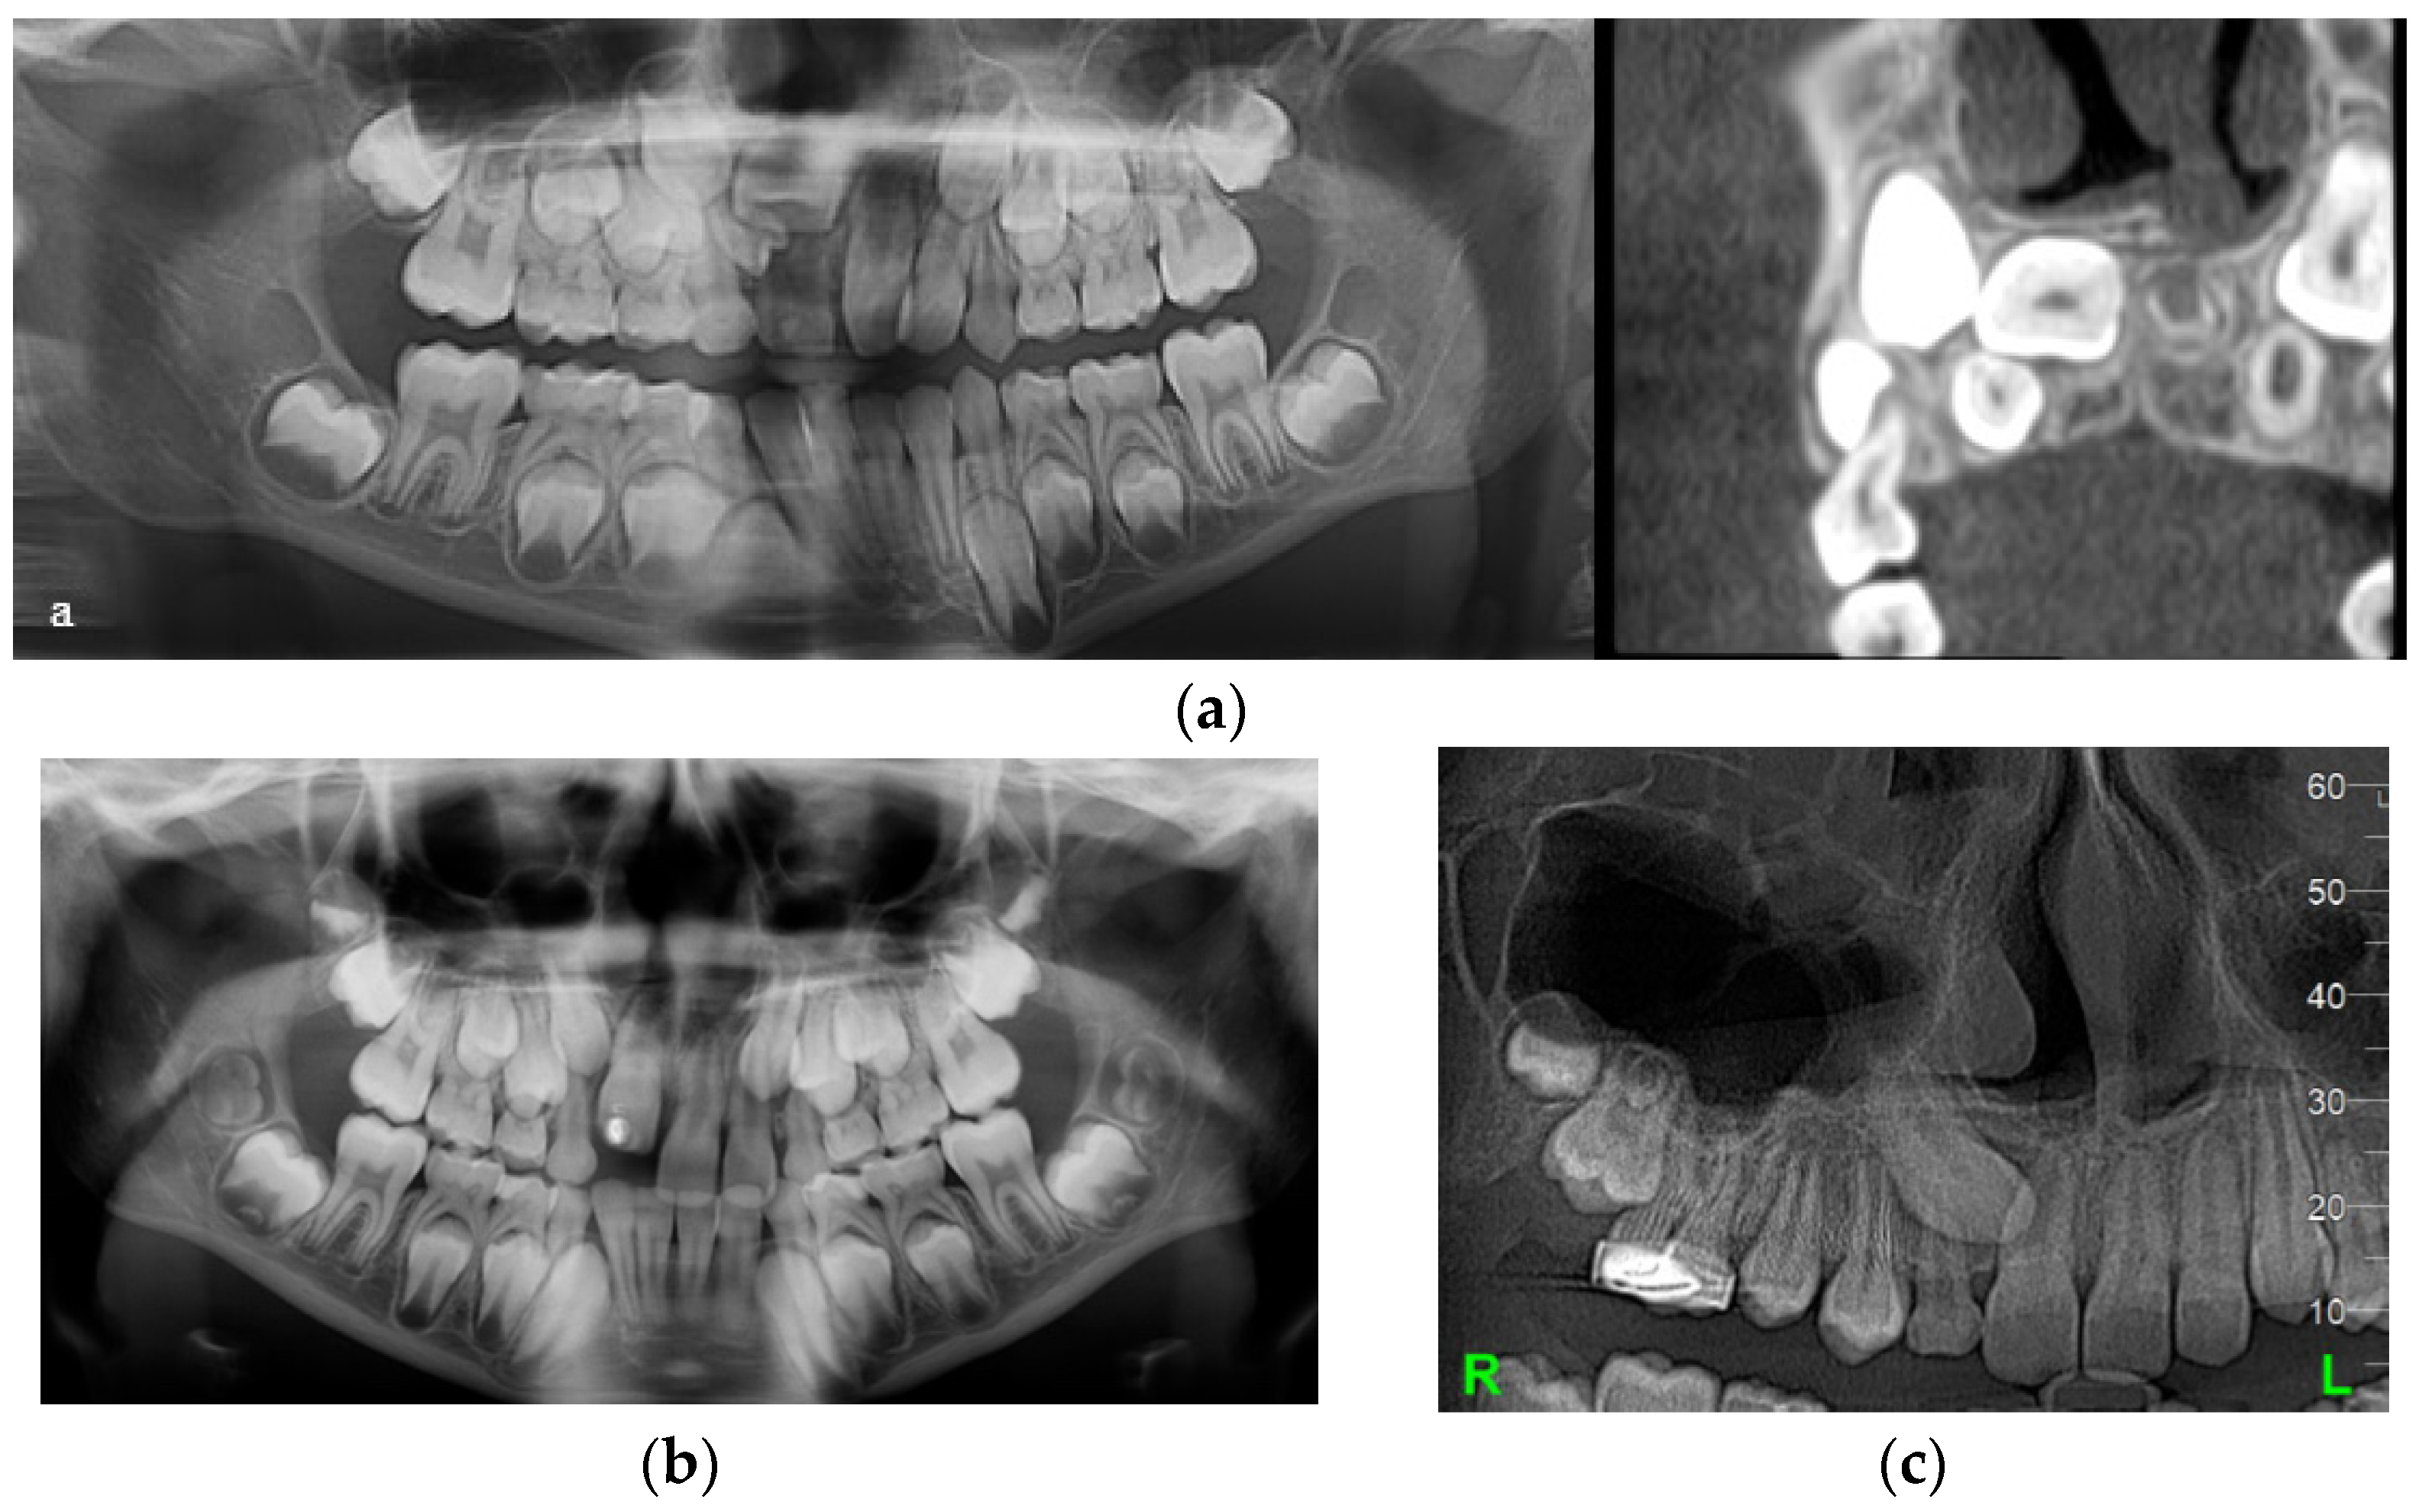

| Case Number | Summary of X-ray Findings |

|---|---|

| Case 1 |

|

| Case 2 |

| Case 3 |

| Case 4 |

| Case 5 |

| Case No./Position of DLs or DCs | 1 Right DL | 1 Left DL | 2 | 3 Right DC | 3 Left DC | 4 Right DC | 4 Left DC | 5 Right DL | 5 Left DL |

|---|---|---|---|---|---|---|---|---|---|

| DL | Y | Y | Y | N | Y | Y | Y | Y | Y |

| DC | Y | N | Y | Y | Y | Y | Y | Y | Y 1 |